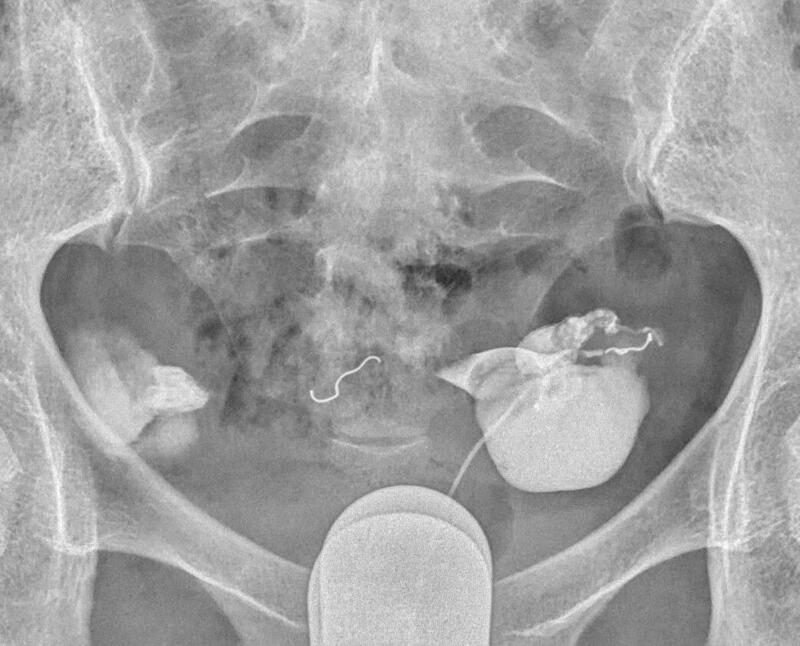

因此致密栓塞不仅是多花钱多受罪,而且还没有栓塞一个合适的弹簧圈栓塞的严实。请看下图双侧输卵管积水两侧输卵管各栓塞一个弹簧圈的术前术后标识。

下面是一例双侧输卵管积水做试管婴儿,2017年在胚胎移植前我给她两侧输卵管各栓塞一个弹簧圈,后来移植后还是双胎。